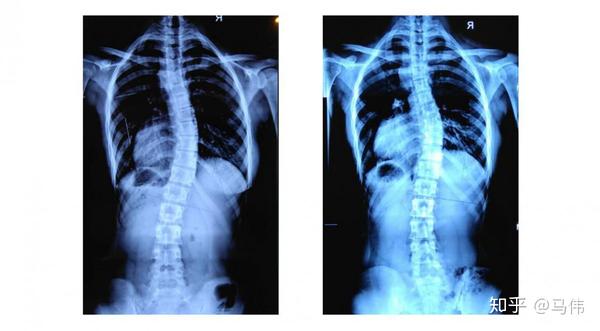

11岁女孩s形脊柱侧弯支具下脊柱中线基本回归至正常

1年前和1年后的x光片对比,颈胸侧弯13°减至5°,腰部侧弯18°减至5

脊柱侧弯运动康复矫正的13岁女孩在2月份和11月份分别拍摄的两张x光片